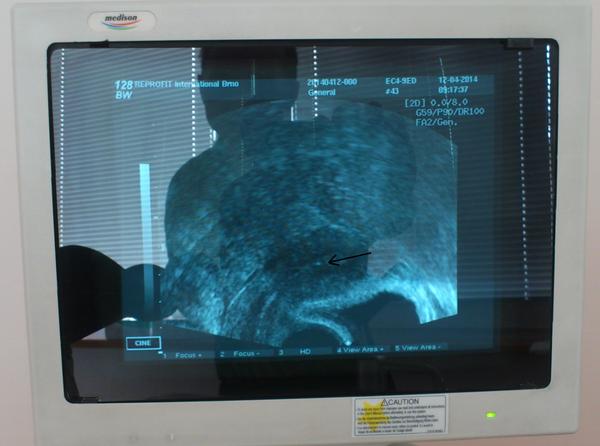

Tak holky dnes kontrola v CARu. Dnes jsem 10 DC a sliznice je 6,4 mm a vajíčko jedno dominantní na pravém vaječníku 10mm. Mám delší tu první fázi cyklu. Měla jsem ji delší i když jsem stimulovala menopurem na IVF. Musela jsem si píchat o dva dny déle. A doktor mi řekl, že ovulace by měla být 17-18 DC. A dle grafu BT a hlenu mi vychází obdobně na 15 DC. V pondělí opět na UZ kde by mi mohli říct jestli ano a nebo ne a popřípadě kdy.

@pistalinda35 Ahoj tak mám dnes za sebou UZ. A představ si včera jsem měla ovulaci a sama!!! Poprvé v životě. A sliznice je teď cca 7,5mm. Takže KET naplánovaný na 12.4. takže jsem zvědavá. Ovulaci jsem cítila, ale nemyslela jsem si, že je to ovulace. Zpětně až jsem si to dnes uvědomila, že to tedy byla ovulace. Myslíš, že už je na sex pozdě dnes když ovulace byla včera cca ve 3 hodiny ráno?

Ahoj holky tak už mám po KETu. V sobotu jsme si byli pro mrazáčka. Nakonec mi KET dělal Otevřel. Vše proběhlo OK. Ale nemám ani čas na to myslet. Buď to vyjde a nebo ne. Včera jsem si vytáhla lehátko a usnula na zahradě, takže mám červený obličej ještě teď. Pak jsem šla vařit. A dnes jsme jeli popřát pradědovi k narozeninám. Zítra se budu muset učit (v pátek jsem byla na pohovoru do nové práce) v úterý pojedu dědečkovi na hrob, který zemřel v Únoru a ve čtvrtek by měl narozeniny. Ve středu budu uklízet a učit se. A ve čtvrtek se také budu učit. V pátek budu celý den na zkoušku v nové práci. V sobotu pojedeme k našim a budeme s nimi grilovat a i s dědou a babičkou. V neděli budeme také u nich. V pondělí se budu zase učit. A úterý, středa, čtvrtek budu jezdit na zkoušku v nové práci. A ve čtvrtek si mám udělat těhotenský test. Když to vyjde budu nejšťastnější, ale když ne tak nastoupím do nové práce a budu se těšit na výstavy se psem a tak. Takže hlavu mám zaměstnanou dokonale. Necítím nic. Cítím se dobře. Jen mě občas píchá v podbříšku. Tak jako u prvního KET. U druhého jsem měla příznaků na dvě stránky A4 a embryjko se ani neuhnízdilo. Doktor říkal, že do úterý mám být v klidu a nesportovat a nic netahat a tak. Že mám expandovanou blastocystu jedničkové kvality a že do úterý se musí chytit. Že pak už není šance. No tak asi tak.